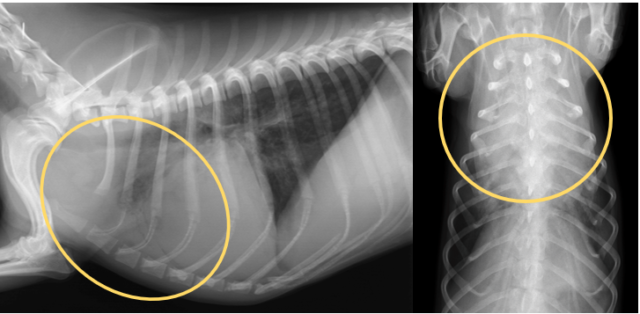

🔍 画像検査で見えた「肺炎」のサイン

レントゲン検査: 肺の前葉〜中葉の腹側(胸の下側)が白く写っていました。これは、重力の影響で誤嚥した内容物が溜まりやすい典型的な部位です。

🏥治療の経過と回復

入院治療の結果、幸いにも白血球数やCRP値は正常化し、レントゲン上の白い影も消失しました。酸素がなくても自力で安定して呼吸ができるようになったため、無事に退院となりました